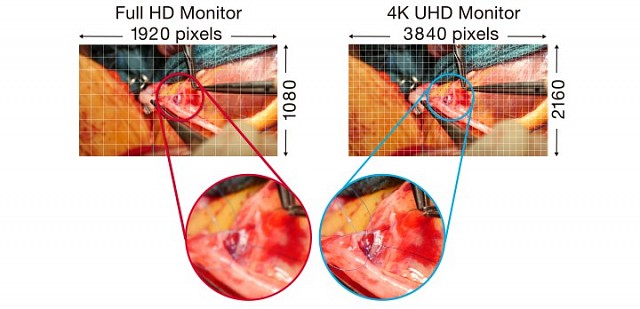

具有4K UHD(3840 x 2160像素)分辨率和高亮度的32英寸宽屏手术监视器。

- 具有稀疏编码(SRSC)的智能分辨率,可显示高清影像

EX3241具有4K UHD(3840 x 2160像素)分辨率和高亮度的32英寸宽屏手术监视器。